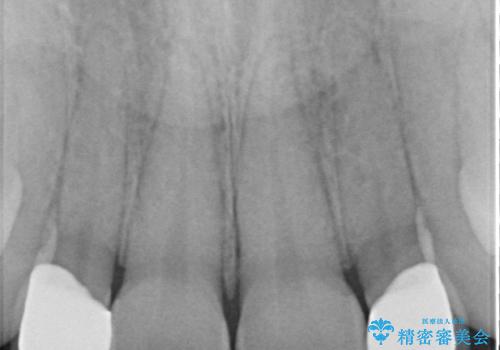

先に矯正治療をすることで、下の前歯を内側に入れることができ、上の歯のセラミックの幅や厚みを取ることができました。